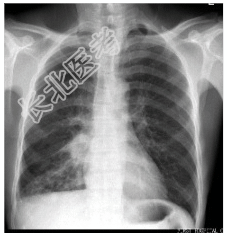

- [材料题] 患者,男性,53岁。咳嗽,咳痰2月余,痰中间或带血丝。患者有吸烟史20余年,每天20支。查体.右下肺呼吸音减弱,可闻及湿啰音。心脏无异常。行胸部平片检查。

- 简答题1、诊断及依据是什么?

- 简答题2、鉴别诊断有哪些?